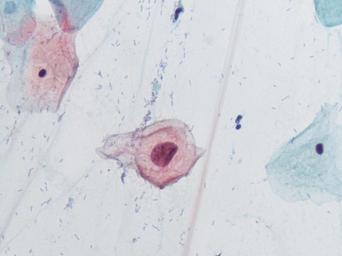

Keywords: lesión intraepitelial escamosa de bajo grado lesiónintraepitelialescamosadebajogrado citología de cuello uterino citologíadecuellouterino citología exfoliativa ginecológica citologíaexfoliativaginecológica citología de cribado citologíadecribado citología anatomía patológica anatomíapatológica bethesda 2001 bethesda2001 osuna cérvix uterino cérvixuterino hpv españa screening lsil enfermedades de transmisión sexual enfermedadesdetransmisiónsexual imágenes de citología ginecológica imágenesdecitologíaginecológica papanicolaou test de papanicolaou testdepapanicolaou tinción de papanicolaou tincióndepapanicolaou Células con núcleo y citoplasma aumentado de tamaño, núcleos irregulares, como plumosos, tendencia al color naranja de muchas células, halos en algunos casos, núcleos dobles en otros, algunos núcleos hipercromáticos. Células con núcleo y citoplasma aumentado de tamaño, núcleos irregulares, como plumosos, tendencia al color naranja de muchas células, halos en algunos casos, núcleos dobles en otros, algunos núcleos hipercromáticos.